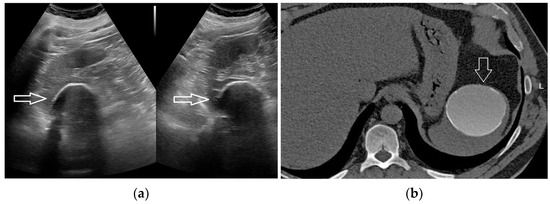

2.5. Hematoma and Abscess